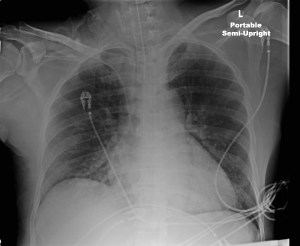

A couple of weeks ago a physician was examining me and noticed that I was no responding. He checked my legs and noticed I was bleeding all over. my stool was running and was full of blood. I was taken to ICU and the set of x-rays taken showed my LUNGS FULL OF BLOOD (refer to image one) The physician was very apologetic and told Issam and the family that there is nothing much he could do. The next day the x-rays showed my LUNGS FULLY CLEAR OF ANY FLUIDS AND VERY HEALTHY.  The same physician and many others were amazed, everyone was in awe. It was A MIRACLE CONFIRMED BY ALL !!! PRAISE THE LORD … MY JOURNEY CONTINUES …

” Today a lung expert evaluated Sami. He called me in amazement as to what has happened between March 5th and 6th in the ICU. He told me that he has never seen anything like this, and that this was a real miracle. Attached are copies of the X-rays before (March 5th) and after (March 6th). On the March 5th X-ray you see a white lung suggestive of a massive bleed / pneumonia on March 6th, you see clear lungs. The lung expert was amazed but after all the prayers, I was not. Praise the Lord. ”Â